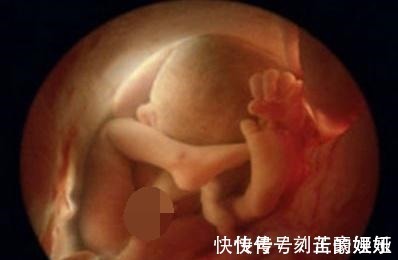

产妇|身怀五个月孕妇下身”见红“误以流产,急忙到医院却让医生憋着笑

昨天五点多快下班的时候一位挺着肚子的产妇哭着喊进来,说医生求你救救我的孩子,这可把值班的护士吓坏了,急忙跑过去想问问产妇怎么了,身体哪里不舒服,一边用急救电话呼叫医生,孕妇说怎么办我才怀孕五个月,刚刚在上厕所的时候,看见裤子上有血,觉得自己可能流产了,孕妇一脸慌张,几乎要哭出来了,这时候医生来了,产妇情绪激动,怕引起大出血,先稳定一下产妇的情绪。

在给产妇做手术之前,先给给产妇做了各项指标检查,可是经过检查发现产妇并没有流产,幸亏给做了检查,不然打了麻药会给宝宝造成很大的伤害,原来她并不是先兆流产,而是急性膀胱炎导致的尿血!通俗一点她这“见红”是憋尿给憋出来的!这让在场所有的医护人员真的是医生哭笑不得。

事后了解后,也是觉得这妈妈够拼的啊,怀孕五个月还在上班,虽然做的工作不是很重,但还是比较认真负责的,因为经常做事的有尿,不是很急都不去上厕所,每次都是快憋不住了才去,因为孕期本来就尿频,她说每次都排出量不多,不想浪费时间上厕所,干脆憋着然后一次性排出去。